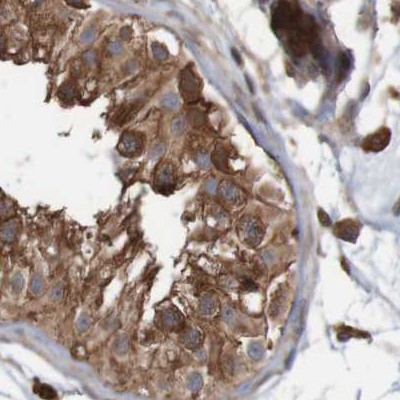

Immunohistochemical staining of human cerebral cortex, colon, lymph node and testis using Anti-ARHGEF11 antibody HPA012037 (A) shows similar protein distribution across tissues to independent antibody HPA011026 (B).